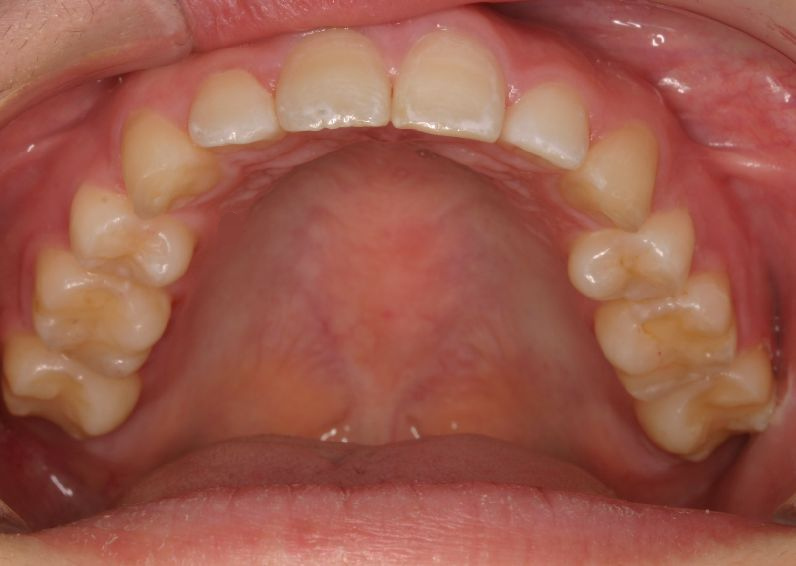

Case 2

主訴:  噛みにくい

診断:  アングルⅠ級 叢生

治療方針:

患者さんは26歳の女性で、上下顎の叢生による審美障害と咬合異常を訴えた。セファロ分析の結果、U-1 to FHおよびL-1 to Mandibularは1S.D.を超えて小さい値であった。その為、上下顎の叢生量は大きいが、上下前歯部の舌側傾斜による口元の落ち込みを防止する目的で、非抜歯で治療を行うことにした。

治療期間: 1年4カ月

費用:

診断費30000円、装置費用600000円、保定装置費用50000円、月1回の調整費4000円  (全て税別)

【 治療前 】

【 治療後 】